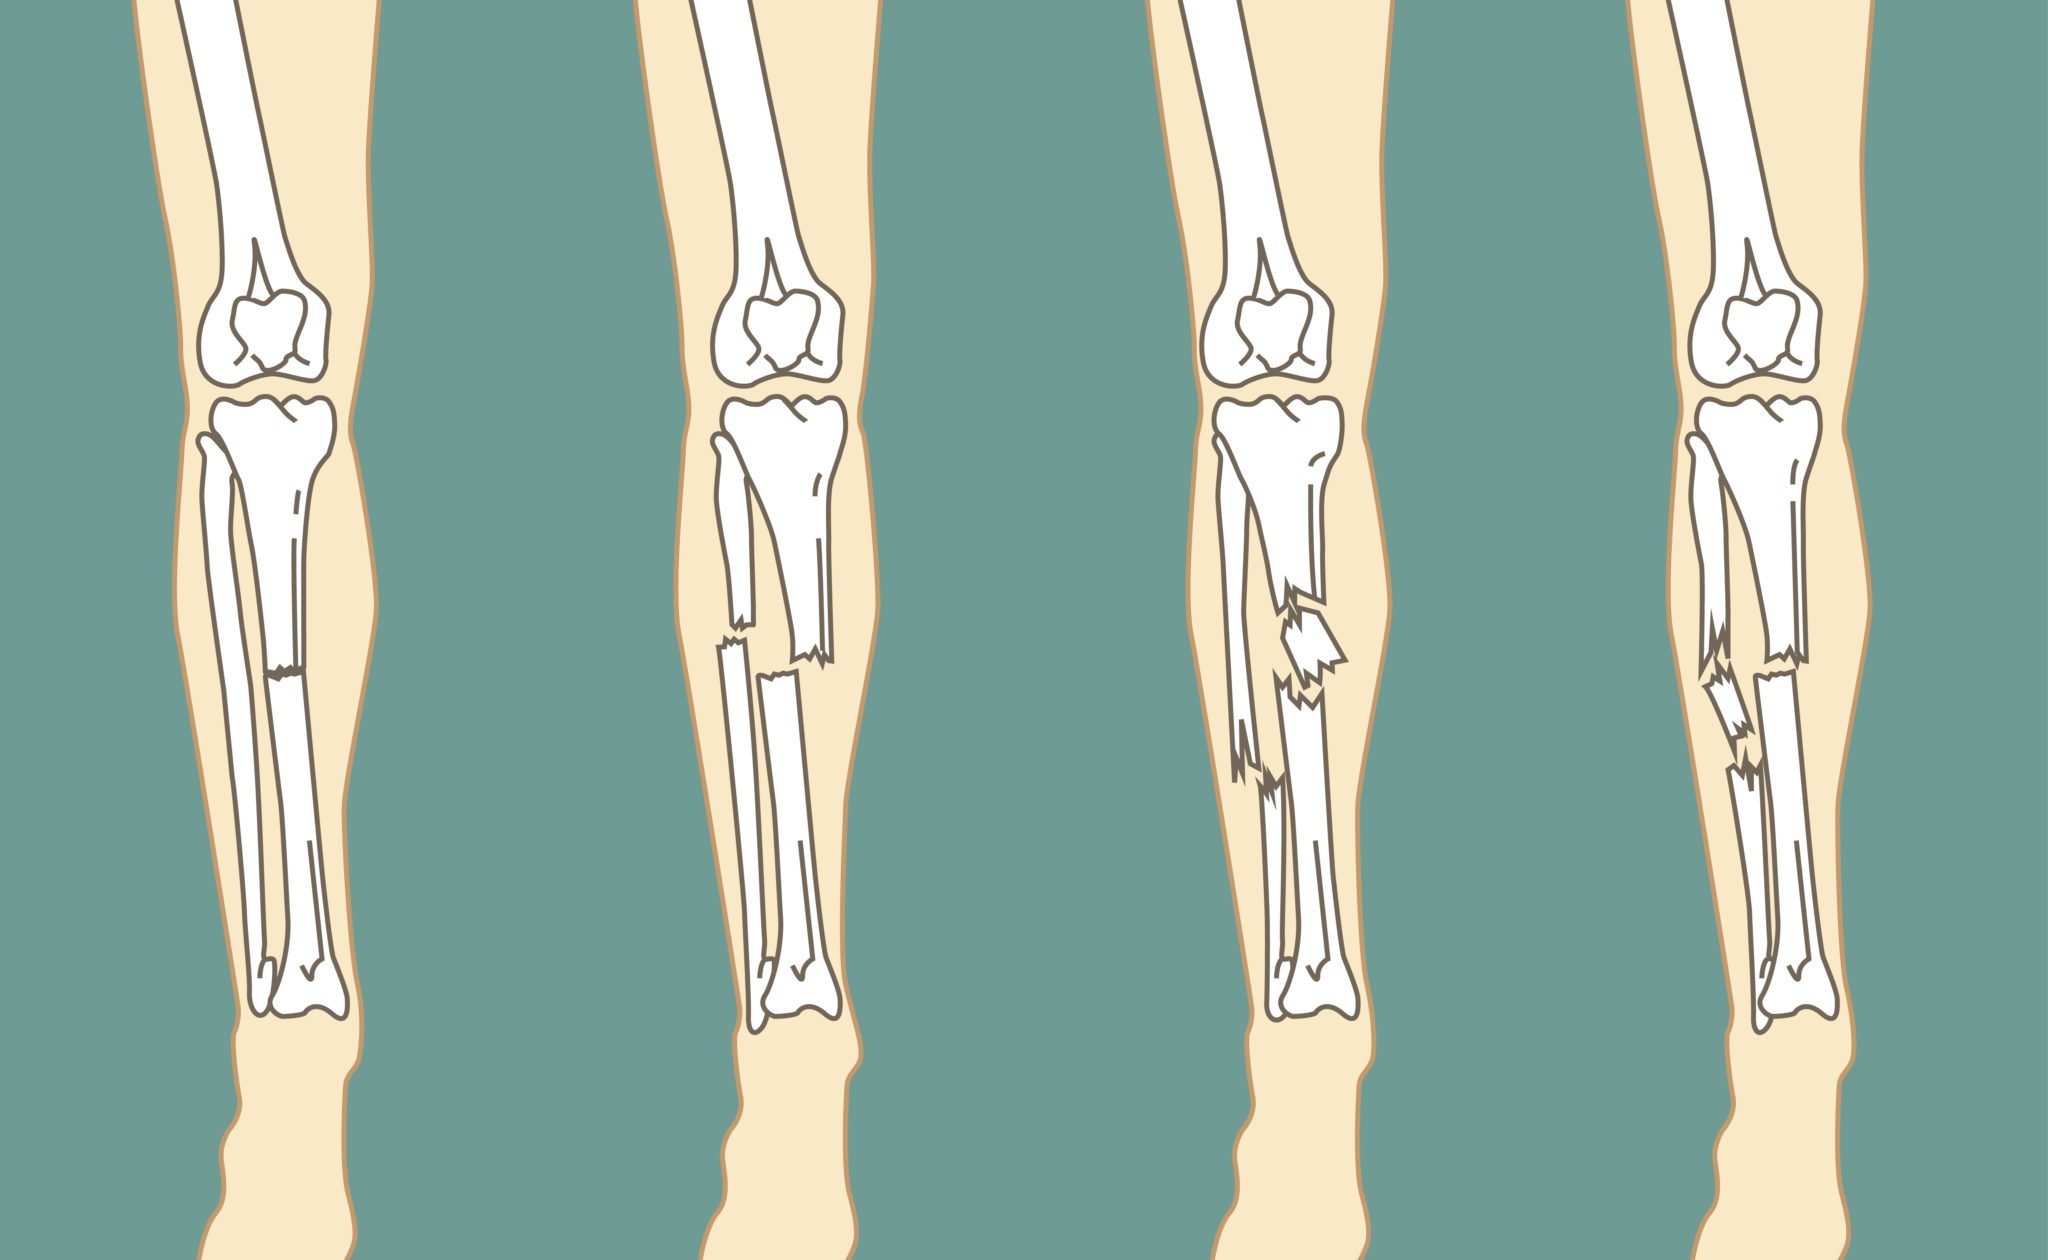

Основные симптомы перелома ноги

Выявить такое опасное повреждение можно по определённой симптоматике. При этом в каждом отдельном случае её интенсивность будет индивидуальной в соответствии со степенью тяжести полученной травмы. Но в любом случае у больного отмечается характерный хруст, сильные болевые ощущения, отсутствие возможности встать на ногу, а также следующие признаки:

- Неестественное положение нижней конечности.

- Ограничение движения.

- Отёчность в месте повреждения.

- Неестественное сгибание конечности в месте повреждения.

- При открытой форме отмечается разрыв мягкой ткани с выходом кости наружу.

- Многочисленные гематомы и внутренние кровоподтёки.

При появлении таких тревожных симптомов следует как можно скорее обращаться за квалифицированной помощью к специалистам. Доктор сможет поставить точный диагноз, составить план лечения и последующего восстановления. Ни в коем случае при такой ситуации нельзя бездействовать, поскольку это лишь усугубит ситуацию и приведёт к осложнениям. Обращаться за качественной восстановительной программой вы всегда можете в наш частный реабилитационный центр «Исток» в Беслане.